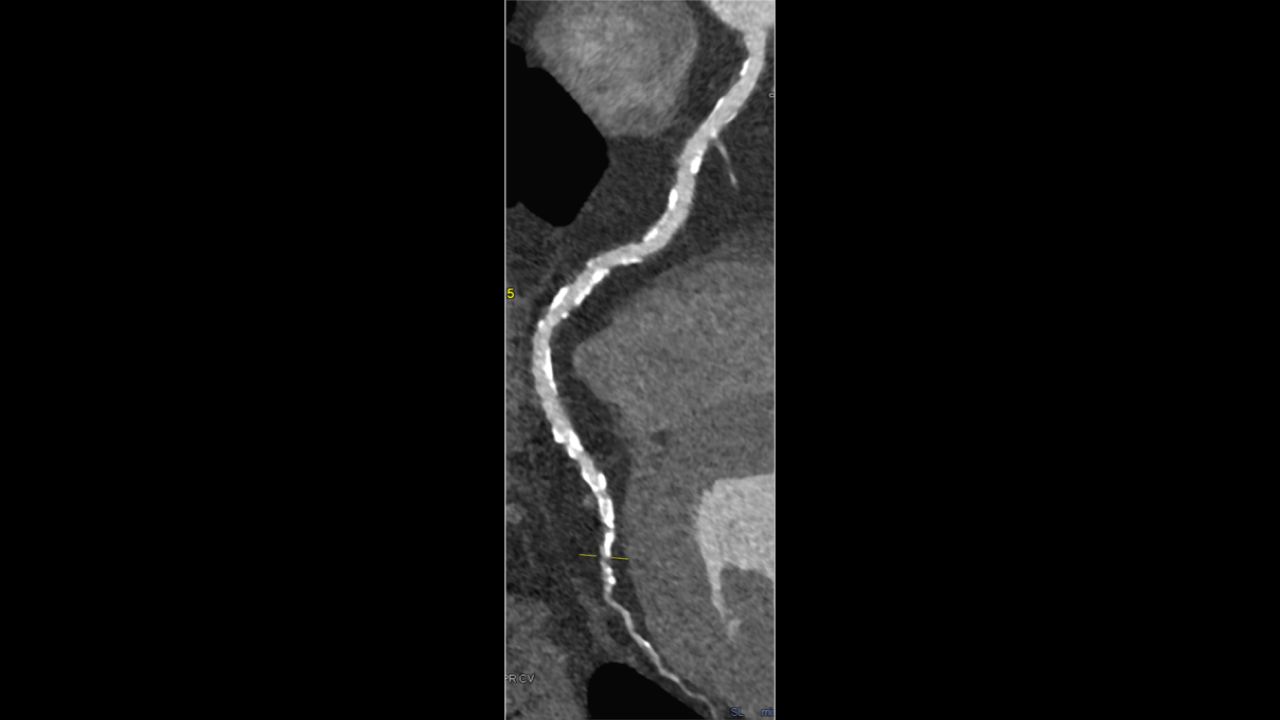

Illustrative Case Example:

A 48-year-old male with a CAC score of 6889 underwent CCTA using PCCT. Despite the high calcium score in the RCA, the RCA was shown to have minimal-mild stenoses. The LAD and LCX was shown to have moderate-severe stenoses.

Whilst this case showed areas of moderate-severe stenoses in the LAD and LCX requiring subsequent PCI. the RCA findings provides a good example of potentially right-siting patients and avoiding catheter angiography with the use of PCCT. This has been supported with previous publications as referenced.